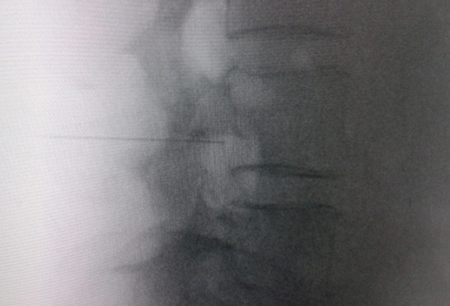

El acceso por vía transforaminal es el más utilizado (4). Se coloca al paciente en decúbito prono con una almohada a nivel abdominal para revertir la lordosis fisiológica. Las agujas o cánulas de radiofrecuencia que utilizamos con más frecuencia son de diámetro 20 o 22 G de 98 mm de largo con punta activa de 0,5 o 1 cm. Después de la asepsia con clorhexidina alcohólica y la colocación de campos estériles, se realizan enfoques radiológicos en incidencia anteroposterior, oblicuo y lateral. En incidencia anteroposterior y moviendo el arco en dirección cráneo caudal se borra el doble arco del borde inferior vertebral. En incidencia oblicua entre 20 y 30 grados ipsilateral al GRD a tratar, se visualizará la clásica imagen descrita como de “Scotty Dog”, que es resultado de acercar el macizo facetario y la apófisis espinosa al lado contralateral. El punto de entrada será entonces inmediatamente debajo del pedículo. Previa anestesia local con lidocaína al 1 %, la aguja se introducirá siguiendo una visión túnel y no se avanzará más allá de la mitad del pedículo en esta proyección con la finalidad de prevenir la lesión neural. En proyección lateral, se introducirá en el techo del neuroforamen

(Figuras 1 y 2) pero la localización final será determinada por la estimulación nerviosa sensitivo-motora. La estimulación sensitiva consiste en provocar parestesia o dolor en el territorio afectado con una estimulación entre 0,3-0,6 v. Durante la estimulación motora se pueden provocar fasciculaciones en el territorio afectado con un voltaje del doble al necesario para provocar las parestesias. Si se desea realizar una denervación intraganglionar, promulgada por algunos autores, la estimulación tanto sensorial como motora será positiva a menos de 0,3 v. Por tratarse de un procedimiento más doloroso, se aconseja administrar anestésicos locales después del estímulo doloroso y antes de realizar el tratamiento. La impedancia deberá mantenerse por debajo de 450 ohms, lo que se consigue infundiendo solución salina previa a la RF (4). La utilización de contraste constituye una buena práctica, ya que descarta la posición intravascular e intratecal de la cánula de radiofrecuencia.

Fig. 1. Vista radiológica de perfil que muestra una cánula de radiofrecuencia en el ángulo anterosuperior o techo del neuroforamen, topografía aproximada del ganglio de la raíz dorsal

Fig. 2. Imagen radiológica anteroposterior de una cánula de radiofrecuencia posicionada en neuroforamen L4-L5, en el llamado triángulo de seguridad, después de la inyección de contraste. Se observa un engrosamiento del radiculograma a nivel del techo del neuroforamen, que podría corresponder al ganglio de la raíz dorsal de L4